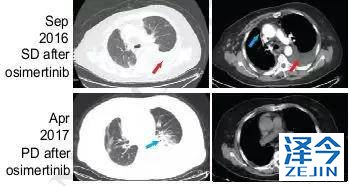

因此,患者开始接受每日80mg的奥西替尼AZD9291治疗,患者在一个月内达到了病情稳定(SD),CA125水平迅速下降,经过8个月的无进展生存期,患者肺左下叶出现新的病灶,胸腔积液增多,病情发展。

布加替尼联合西妥昔单抗治疗,病情长期稳定控制

患者再次基因检测发现T790M-C797S顺式突变,因此在2017年7月开始联合使用布加替尼(90mg/日)和西妥昔单抗(600mg/月),治疗一个月时,患者的疲劳和呼吸困难明显改善,CA125水平明显下降,直到2018年4月病情一直稳定(PFS为9个月),除了轻度疲劳外无其他的不良反应。虽然在2018年4月患者出现脑转移灶,但在2018年9月,患者的胸部病灶依旧得到很好的控制。